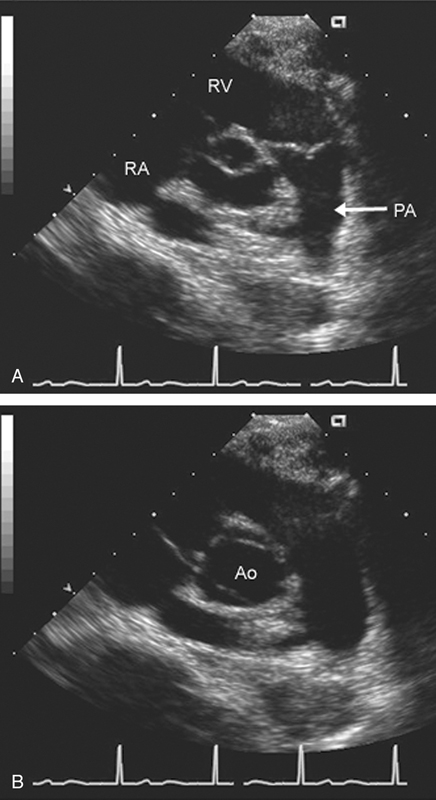

فحوصات تشخيصية لبعض امراض القلب والشرايين التاجية